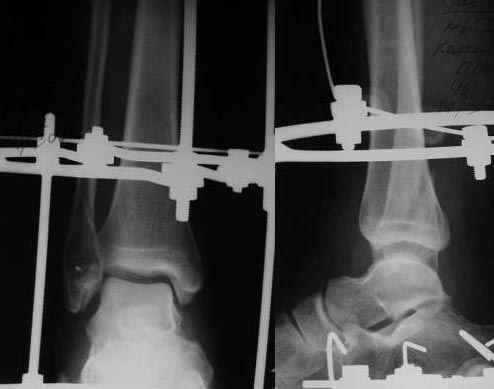

Re: Открытый переломо-вывих стопы.

День-вечер добрый ,Никита.Ваш случай представляется мне довольно типичным,хотя возможно, я чего-то не замечаю.

Мне кажется,что стояние отломков достаточно хорошее,но следует уменьшить дистракцию на 1.5-2мм.Имея опыт лечения подобных переломов могу сказать следующее:

1)Следовало ложить АВФ сразу по ургенству+активный дренаж.

2) по компоновке:вверх обычно ставлю стержень(ставить быстрее,чем перекрест и мягкие не режет)в дистальный метафиз перекрест из спиц с упором к кольцу.кольцо и стержень соединяю планкой дугу на пятке компоную как и Вы.НО провожу спицу с упором с латеральной стороны через головки плюсневых костей.спицу фиксирую к дуге.переднюю и заднюю дуги связываю и+переднюю вяжу к верхнему стержню.получается эдакий сапожок.

3)затем к1.5-2мес ставлю шарниры в проерции оси сустава и начинаю движения(режим легкой дистракции 0.5мм)

4)нагрузку не форсируйте(IMHO)

5)следите за синдесмозом(имел печальный опыт,но в Вашем случае все вроде должно быть нормально)

> 1. Уменьшать ли высоту суставной щели голено-стопного сустава?

> Перестарался я, добиваясь сопоставления дистального отломка

> малоберцовой кости по длине.

Перед этим необходимо стабилизировать дистальный синдесмоз и фрагменты малоберцовой кости двумя спицами. Одну проведите через малоберцовую кость:(VIII,6-12). Вторую - через большеберцовую: VII,3-9 (на на уровне VIII, т.е. синдесмоза нежелательно - рана близко). Встречно-боковой компрессией, используя тягу за VII,3-9, не увлекайтесь: только стабилизируйте синдесмоз. Для фиксации спиц придется низвести вторую (сверху) опору или использовать кронштейны. Псоле этого и устраните диастаз м/у суставными поверхностями.

Опору с пятки убирайте не раньше, чем через 3-4 недели (для дельтовидной связки). От нагрузки на конечность следует воздержаться. Движения в голеностопе рекомендуйте после демонтажа дистальной опоры. Еще через 2-3 недели аппарат демонтируйте и рекомендуйте возрастающую дозированную нагрузку.